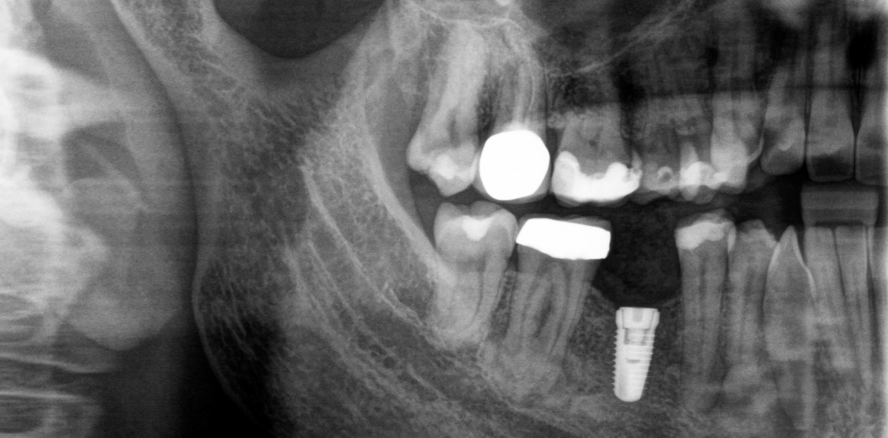

Im OPG sowie im DVT – angefertigt im Rahmen der Implantatplanung – wurden insgesamt fünf apikale Läsionen als Zufallsbefund festgestellt. Eine sklerotische Läsion wurden an den Zähnen 14-15 (Abb. 2) und vier gemischte radiopak-radioluzente Strukturen mit zementdichter Masse und radioluzentem Randsaum verschiedener Größen an den Zähnen 36, 34, 45 und 47 (Abb. 3–5) festgestellt. Die Wurzelfüllung am Zahn 36 war insuffizient und am Zahn 34 bestand radiologisch der Verdacht auf eine überstopfte undichte Wurzelfüllung. Die vestibuläre Knochenlamelle schien intakt zu sein, eine Auftreibung des Unterkiefers lag nicht vor (Abb. 6–8).

Die postoperative Röntgenkontrolle zeigte ein regelrechtes OP-Ergebnis (Abb. 17). Die Patientin kam eine Woche später mit rückläufigen Beschwerden zur Nahtentfernung. Im Intervall und bei vollständiger Beschwerdefreiheit sowie unauffälliger klinischer Untersuchung erfolgte die gewünschte Implantattherapie Regio 46 (Abb. 18). Die Patientin wird zur regelmäßigen Röntgenkontrolle im Rahmen der Nachsorge der zemento-ossären Dysplasie bestellt. Drei Monate später erfolgte die Röntgenkotrolle nach der Implantatfreilegung. Diese zeigte eine gute Osseointegration, sodass das Implantat einwandfrei versorgt wurde. (Abb. 19).